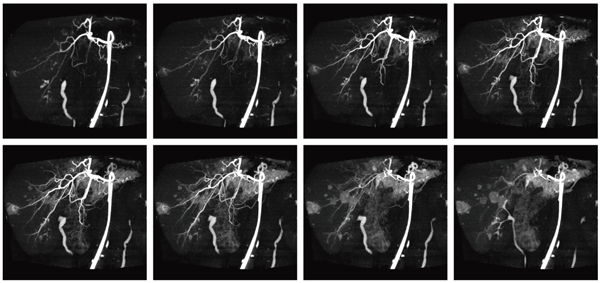

Dynamic Volume Scan(DVS)は,Volume Scanを連続または間歇で複数回撮影することにより,Volumeデータに時間情報を加えた4次元データを取得する撮影法である。DVSは寝台移動を伴わないため,幾何学的な位置ズレのない,臓器の連続した血流情報を得ることができる。この4次元データは任意の方向から観察可能であり,臓器,骨,血管の重なりを避けた評価や,病変の微細な時間変化をとらえることが可能となる。

図2に,肝細胞がん術前検査の例を示す。本症例で使用した造影剤量はわずか20mL(倍希釈)のみであり,従来のInterventional Radiology(IVR)に比べ,造影剤量の低減と検査時間の短縮を図っている。

図2 Dynamic Volume Scanを用いた肝細胞がん術前検査(画像ご提供:医療法人 大雄会様)